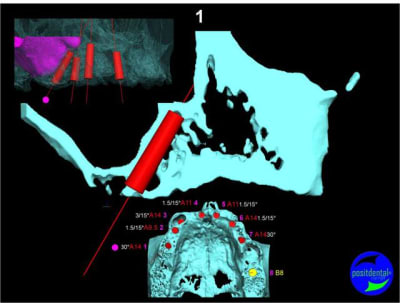

Projet implantaire:

Extraction, pose d’implants Ankylos, pose des piliers Standard définitifs, mise en charge immédiate bi-maxillaire en une chirurgie.

Maxillaire supérieur – extraction 13, 26, 7 implants en MCI, 1 implant en MCR pose summeurs, densification par ostéotme, comblement osseux, bridge provisoire sans fausse gencive avec renfort métallique.

3D

en attendant la pano voici les coupes de la S.I.A.O.